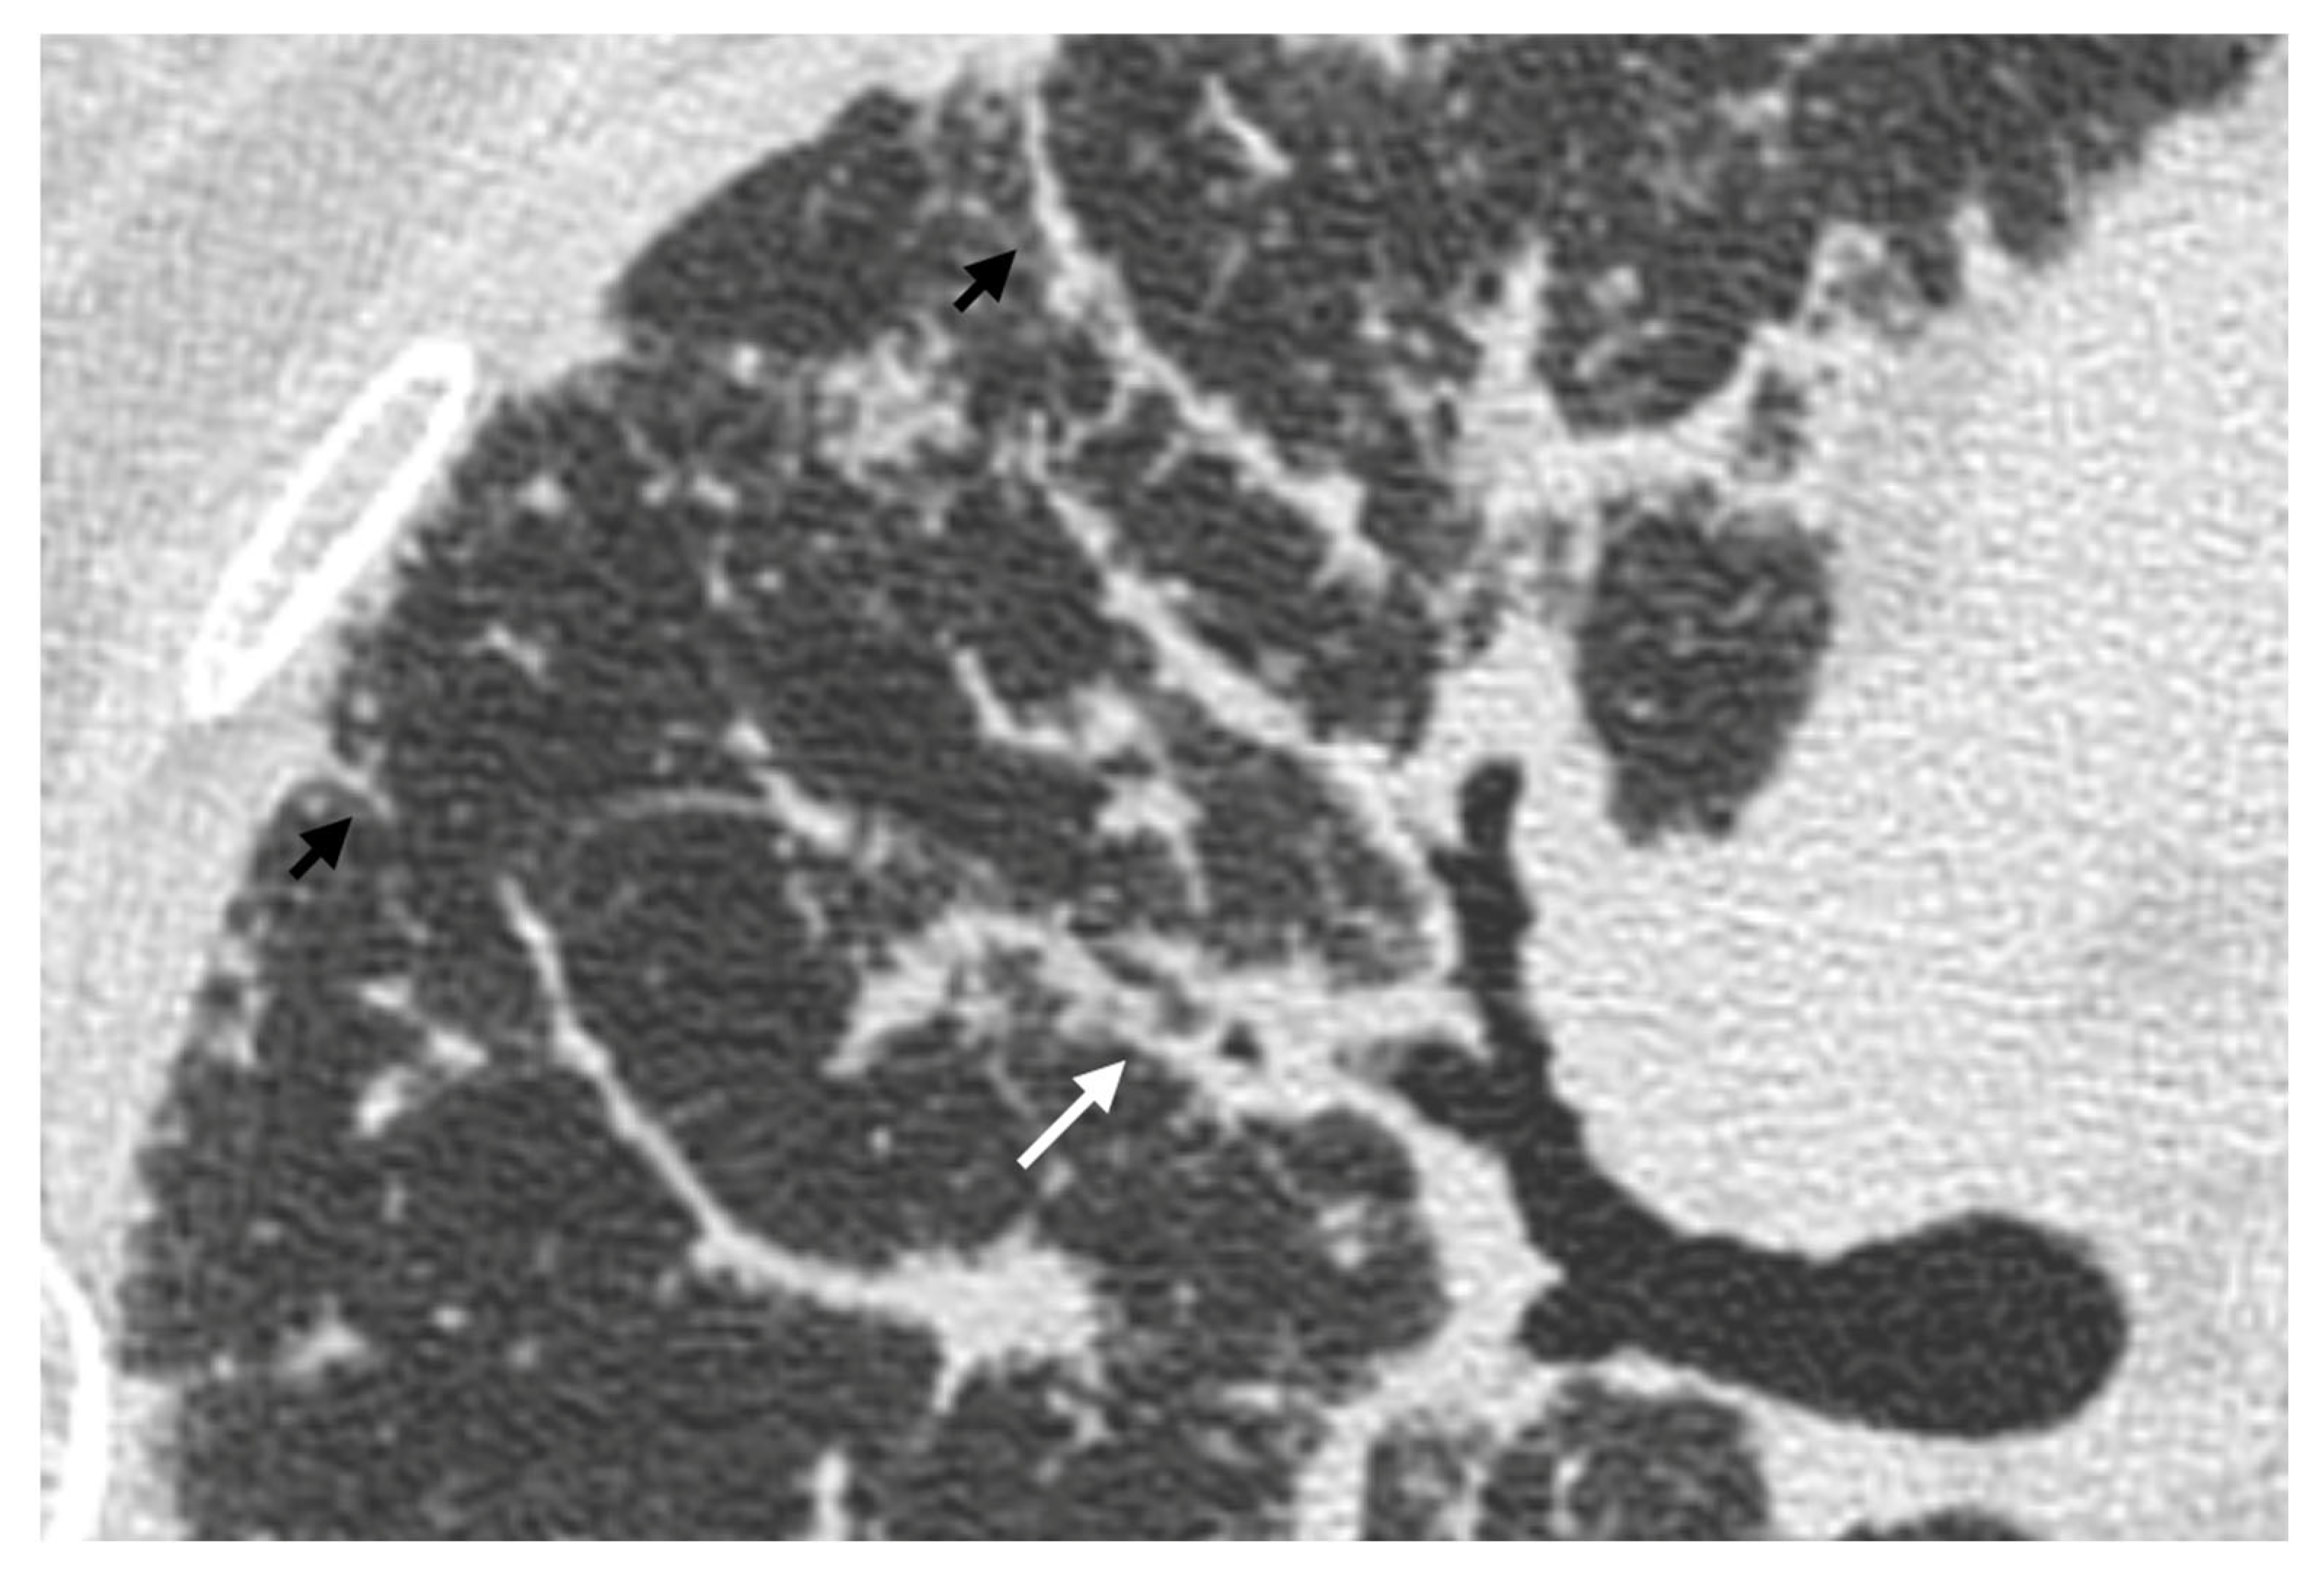

4. Pulmonary Interstitium

4.1. Typical Imaging

4.2.1. Nodules and Masses

| Distribution | Perilympathic (75–90% of cases); bilateral and symmetric involvement, especially in the middle and upper lobes |

| Nodule size | Micronodules 2–4 mm in diameter |

| Morphology | Nodules with well-defined margins, round shape |

| HRCT localization | Peribronchovascular interstitium, interlobar fissures, interlobular septa |

| Evolution | Possible coalescence of micronodules into macronodules over time |